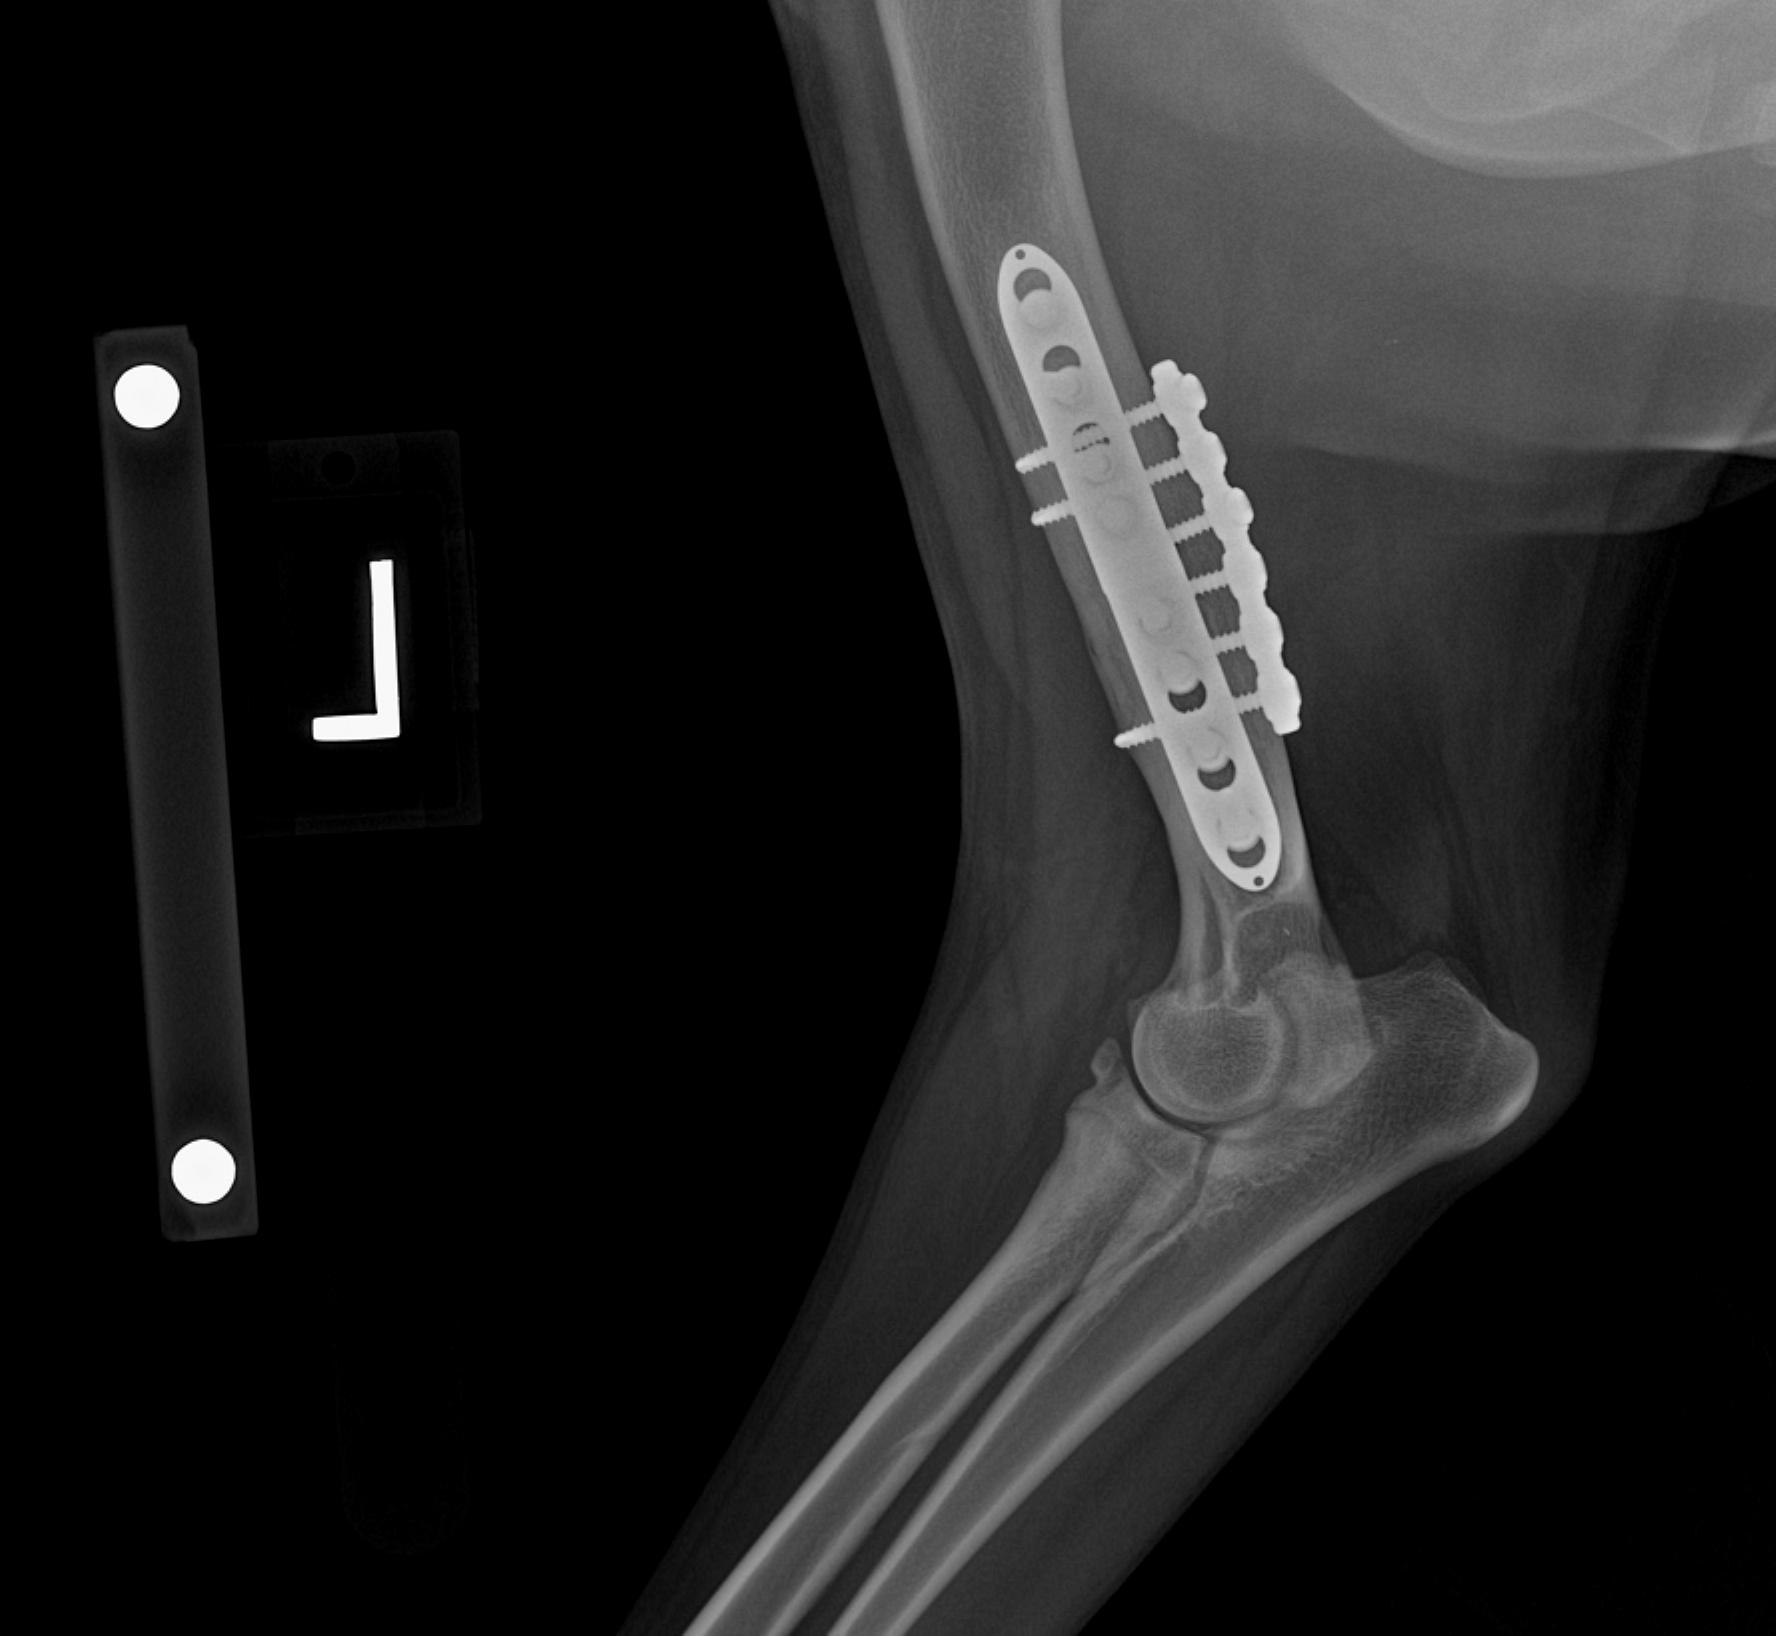

Patient with a Sliding Humeral Osteotomy (SHO).